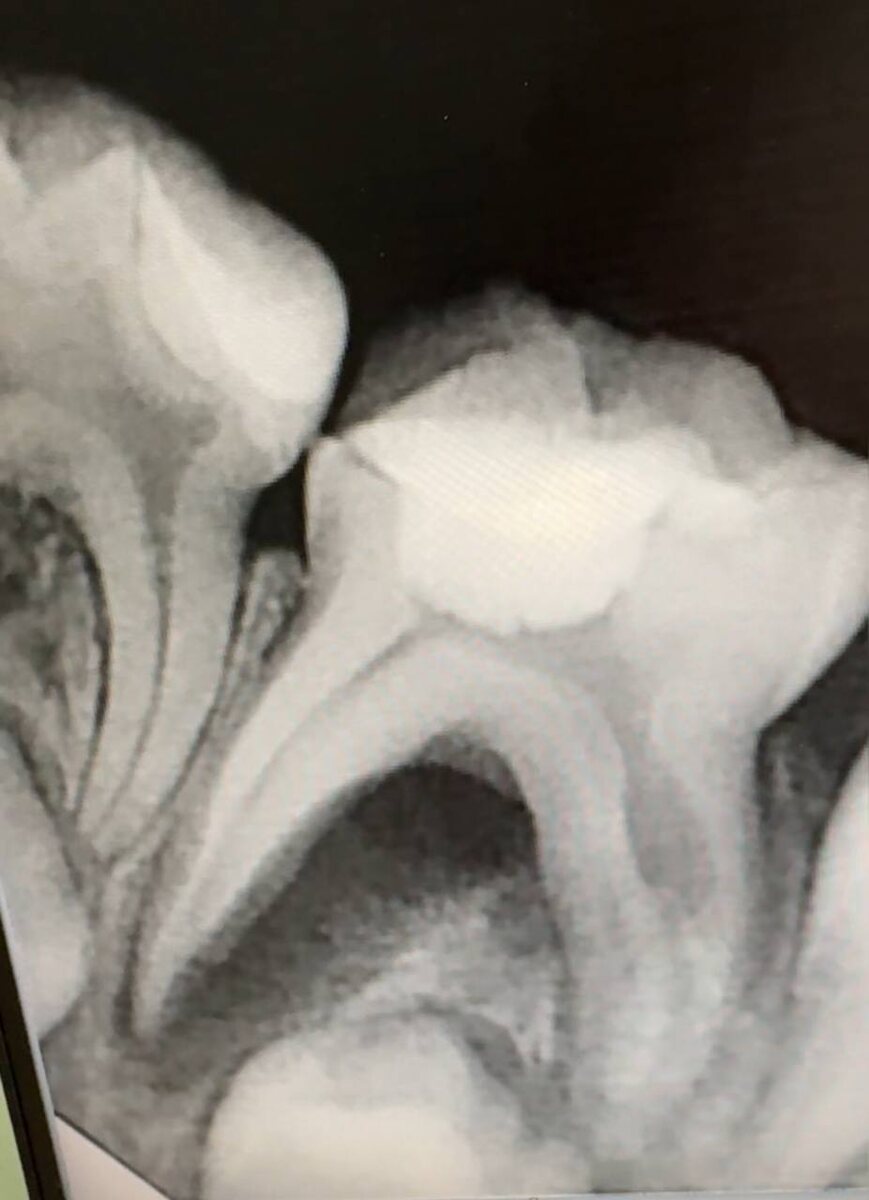

И вот ребенок у меня в кресле, мама решила поменять врача, ее право. Первое, что мы делаем после осмотра- диагностический снимок. И что мы видим?

1. Обратите внимание, листая вбок снимки, вы можете увидеть на втором фото выделенную красным цветом зону очага воспаления. Достаточно обширная, уходит в межкорневое пространство.

2. На третьем фото в одном из корневых каналов видна внутриканальная резорбция.

И 1 и 2 - это показание к удалению зуба. И конечно, эти изменения не могли произойти за 2 недели, на это нужно гораздо больше времени.